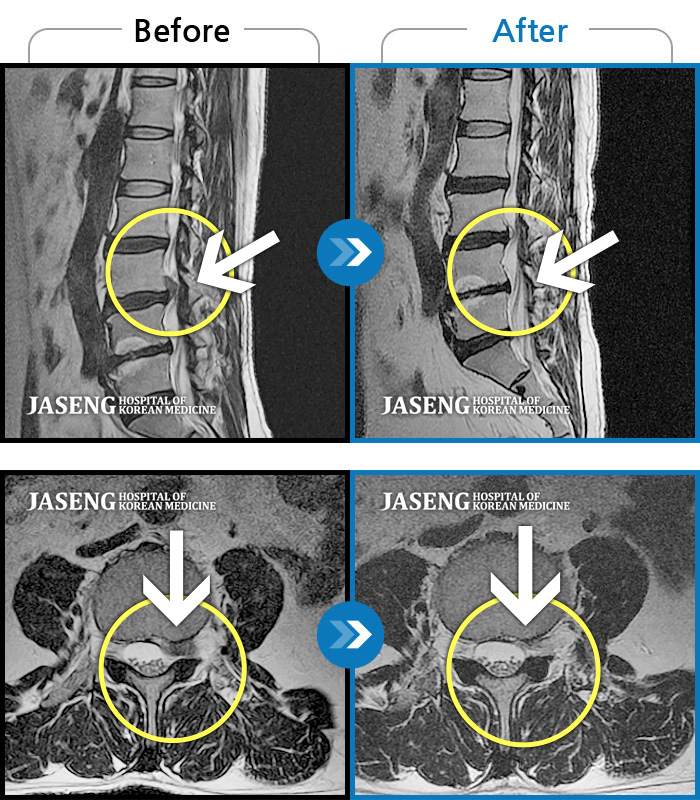

허리디스크

일산 · 김태용 원장

허리와 좌측 하지 방사통이 심하시어 보행이 거의 힘들었다.

촬영시기

2021.03.06 ~ 2021.07.15

2021.07.23